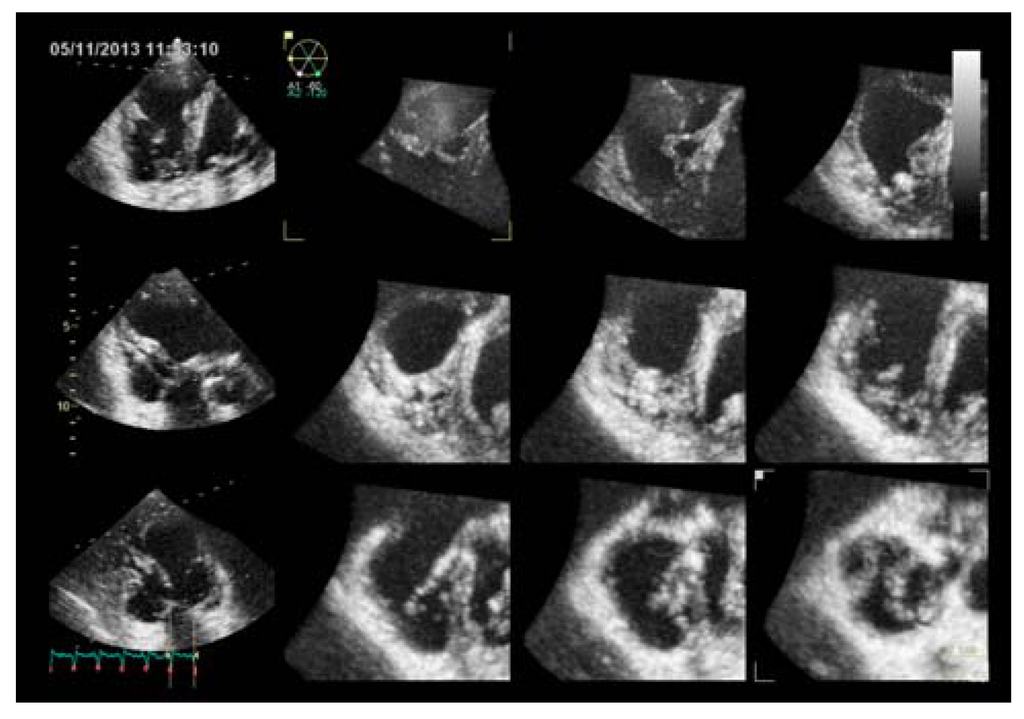

Three-dimensional echocardiography (Figure 3; Videos 1–2) has been demonstrated to be feasible, accurate and reproducible in measuring RV volumes and ejection fraction in adults [,,,,,,,,], as well as in children [,]. Recent studies demonstrated a close correlation between 3D-echocardiography and CMR in measuring RV volumes and ejection fraction [,,] (Table 1). However, 3D echocardiography appeared to underestimate RV volumes in comparison to CMR []. Anyway this underestimation is systematic [], confirming the good agreement between the two techniques and the accuracy of 3D echo. 3D echocardiography confirmed the correlation between RV volumes and gender, age, and body size, previously demonstrated by CMR [] (Figure 4).

Figure 3.

Three-dimensional echocardiographic visualization of the right ventricle in a healthy subject. (A) Multislice view showing three apical views and corresponding short axis. (B) Right ventricular beutel in end-diastole and end-systole and the corresponding time-volume curve. EDV = end-diastolic volume; ESV = end-systolic volume; RV = right ventricle.

Three-dimensional echocardiography demonstrated to be superior in comparison to conventional echocardiography in identifying RV dysfunction in patients with PH [] (Figure 5; video 3). Recently, RV function assessed by 3D echocardiography has been reported to be prognostically important in patients with acute pulmonary embolism [].

Figure 5.

Three-dimensional echocardiography of the right ventricle in a pulmonary hypertension patient, showing three apical views and corresponding short axis.